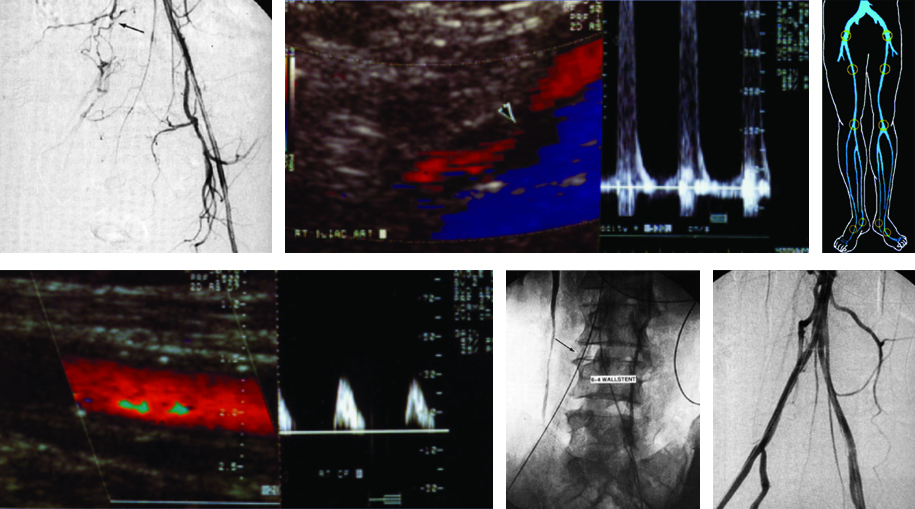

Estenosis aorto ilíaca

Produce circulación por colaterales de las arterias lumbares con ramas glúteas y de la arteria femoral profunda. Los síntomas incluyen claudicación intermitente de la zona glútea, muslo y pantorrilla. En el examen DC existen bajas velocidades con pérdida de la deflexión diastólica y bajas velocidades en ambas arterias femorales comunes (Fig. 16).

Estenosis ilíaca

Produce circulación por colaterales de las arterias con ramas glúteas y de la arteria femoral profunda. Los síntomas incluyen claudicación intermitente de la zona glútea, muslo y pantorrilla. Típicamente aparece una diferencia espectral entre las femorales comunes al comenzar el examen (Fig. 17).

Estenosis femoral

Es la más frecuente, ocasiona dolor en la pantorrilla. El DC es característico (Fig. 18).

Oclusión femoral

Durante la oclusión desaparece la señal DC en el vaso afectado, con ausencia de análisis espectral (Fig. 19).

Una colateralización primaria aceptable está dada por velocidades de pico sistólico superiores a 30 cm/ seg, adecuadas velocidades de fin de la diástole y un índice tobillo-braquial superior a 0,6. El informe del estudio debe incluir siempre el lado evaluado por separado; se puede agregar un gráfico en donde se marque el lado y nivel afectado.

De no contar con información sobre el tipo de cirugía realizada, el médico radiólogo llevará a cabo una anamnesis al paciente sobre el tema y la sintomatología actual; asimismo lo examinará en búsqueda de cicatrices que le permitan reconocer la técnica empleada. Luego procederá a evaluar el tipo de injerto y la topografía del bypass, realizará la medición de las velocidades de flujo en las anastomosis y en el injerto, y procederá a medir el índice tobillo-braquial. Identificará el tipo de bypass femoral. Durante el examen se evaluará la velocidad de pico sistólico en el sector de las anastomosis y en el injerto. En el período postquirúrgico el flujo típico es de hiperemia, con diástoles prominentes. Al cabo de dos meses se establece un patrón trifásico típico. La velocidad en el bypass debe ser superior a 40 cm/seg (Fig. 21).

Angioplastia con stent ilíaco

Se utiliza en las estenosis de las arterias ilíacas, su colocación a nivel femoral o poplíteo no tiene buenos resultados a largo plazo, se utilizan en pacientes con alto riesgo quirúrgico10 (Fig. 22).